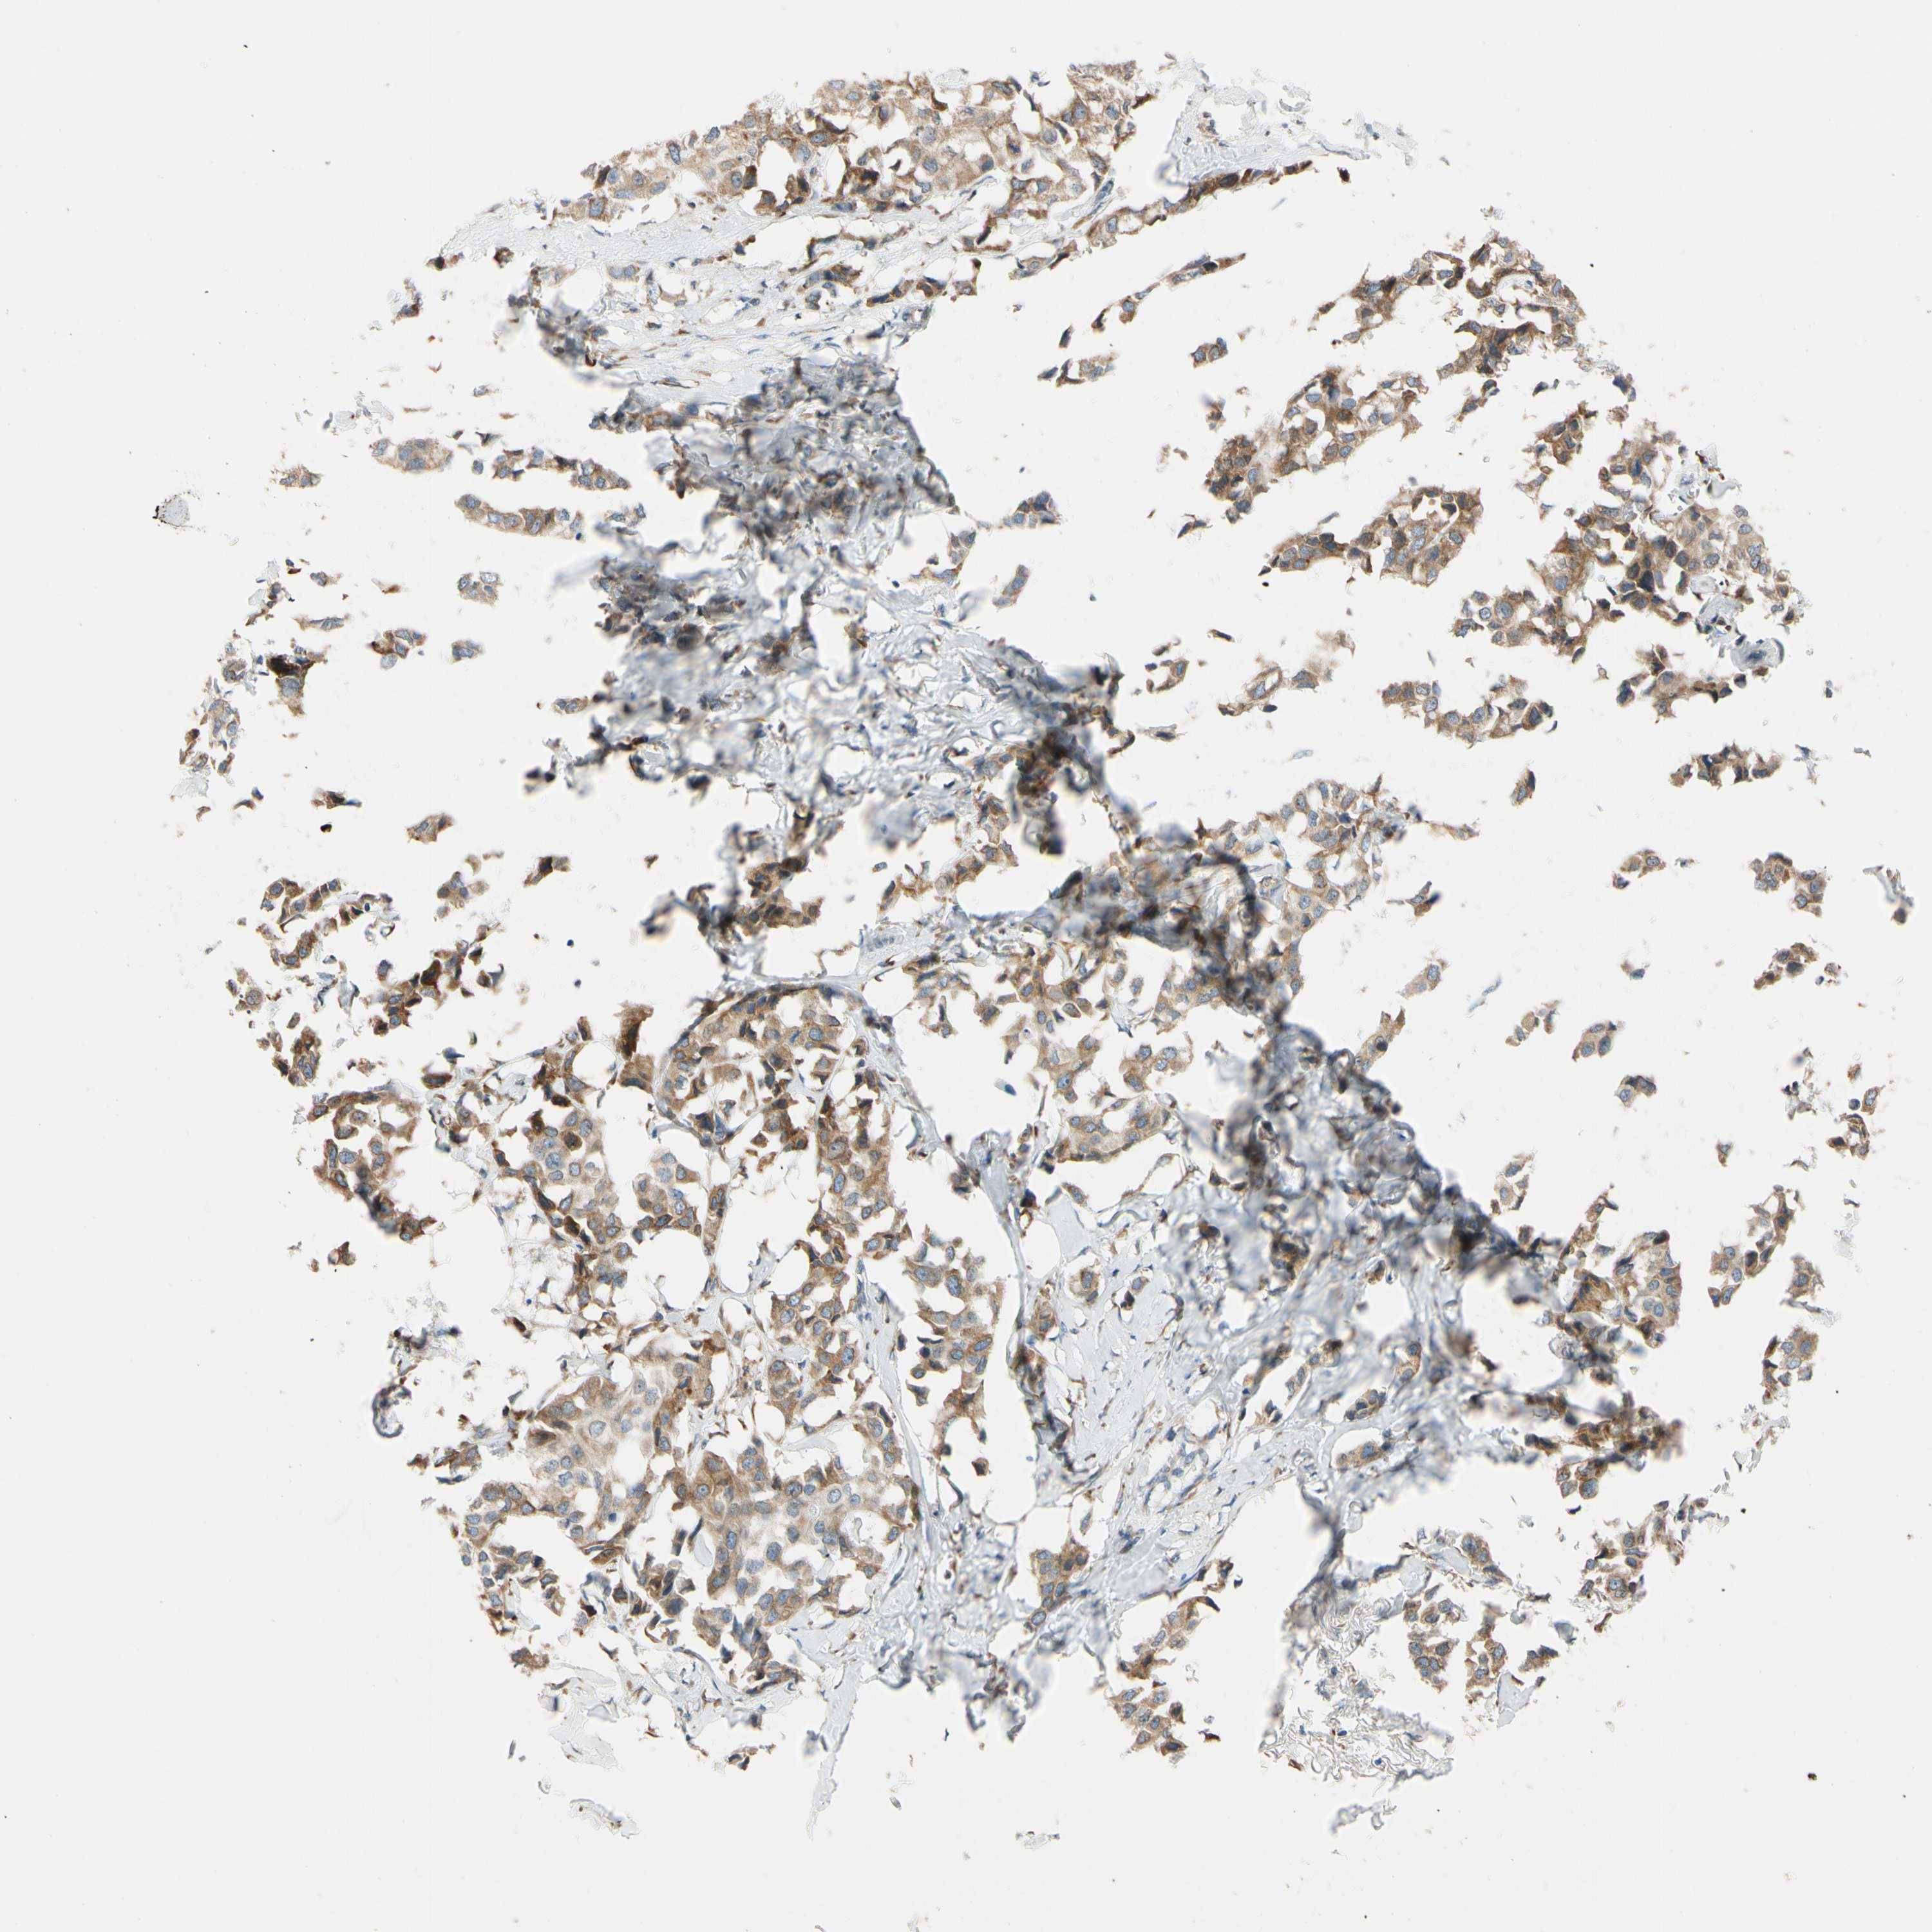

BRCA TCGA BRCA VALIDATION PROTEIN EXPRESSION

ANTIBODIES

AND

VALIDATION